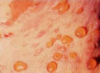

What is the skin condition causing blisters to form that is associated with a type II hypersensitive reaction? What immunoglobin drives this disease?

Bullous pemphigoid and pemphigus vulgaris

Remember that type II hypersensitivity reactions are mediated by antibodies. These conditions are caused by IgG that attacks cell-cell junctions, leading to blistering of skin.